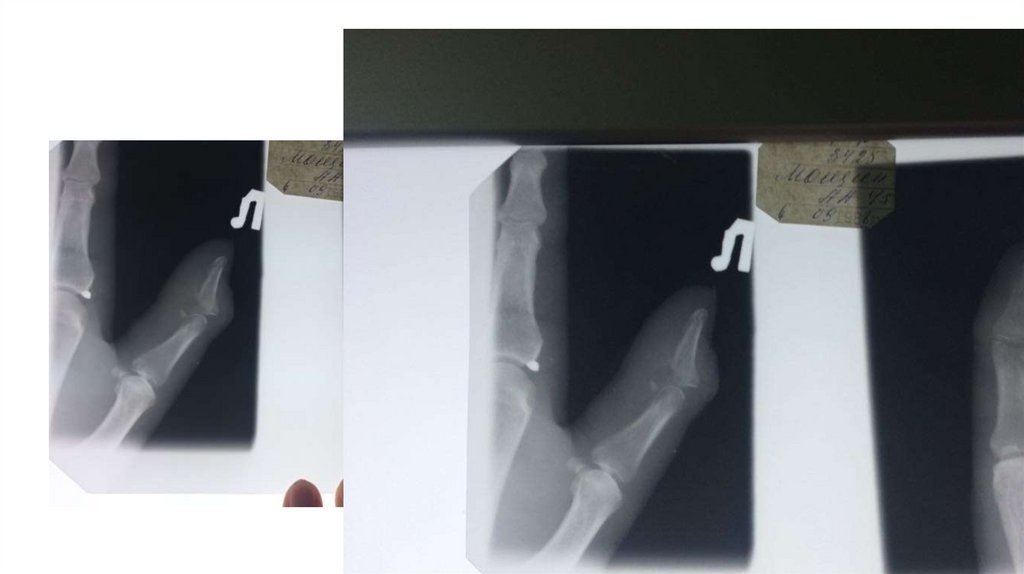

Воспалительные заболевания опорнодвигательного аппарата

заболевания опорнодвигательного аппарата»